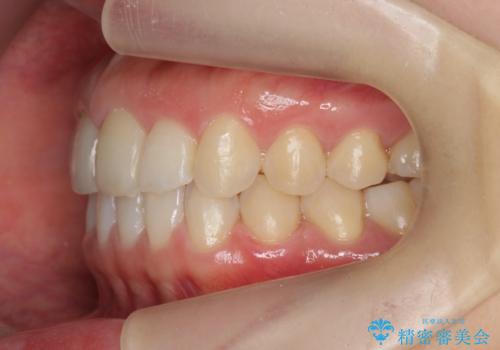

前歯のガタつきをきれいに マウスピース矯正治療

- 「前歯のガタつきをきれいにしたい。」と矯正治療を希望され来院されました。

前歯のガタつきをワイヤー部分矯正、上顎前突の咬合関係を後方移動することで理想的な咬合関係を確立します。

上顎の全体的な後方移動を実現するためにマイクロインプラントを併用したゴムかけを行ったことで理想的な咬合関係を確立することができました。